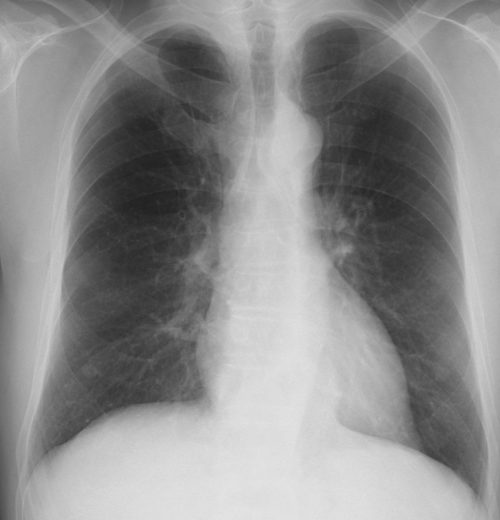

(シルエットサインの読み方) 典型的な均等影の所見、侵されている肺区域を考慮する時、右心辺縁は鮮明にみることができシルエットサイン陰性、右の横隔膜は不鮮明でシルエットサイン陽性のためこの均等影はS8とS10にあることが断定できる(写真からはS7、9も含まれて下葉全体に及ぶ肺炎と推定可能)。